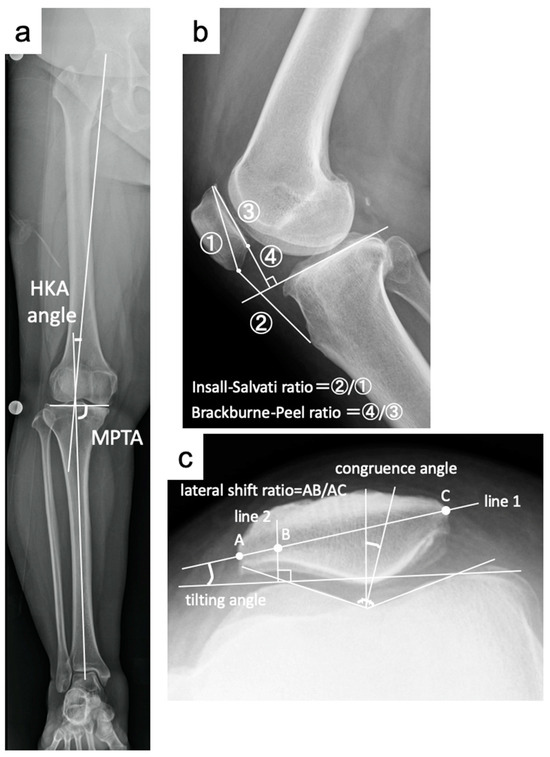

2.2. Radiological Evaluation

| HKA angle (°) | −5.0 ± 2.6 | 3.4 ± 1.6 | <0.001 * | −4.3 ± 2.0 | 4.0 ± 1.6 | <0.001 * |

| MPTA (°) | 84.1 ± 1.8 | 91.6 ± 2.0 | <0.001 * | 84.6 ± 2.4 | 92.3 ± 2.6 | <0.001 * |

| IS ratio | 1.11 ± 0.13 | 1.11 ± 0.14 | 0.53 | 1.15 ± 0.17 | 1.15 ± 0.17 | 0.95 |

| BP ratio | 0.85 ± 0.08 | 0.71 ± 0.10 | <0.001 * | 0.88 ± 0.11 | 0.75 ± 0.10 | <0.001 * |

| tilting angle (°) | 8.6 ± 3.7 | 5.7 ± 3.6 | <0.001 * | 7.9 ± 3.6 | 6.9 ± 4.2 | 0.02 * |

| lateral shift ratio | 12.6 ± 4.8 | 11.0 ± 5.5 | 0.07 | 12.5 ± 5.2 | 12.1 ± 6.0 | 0.69 |

| congruence angle (°) | −5.8 ± 10.6 | −6.3 ± 10.4 | 0.55 | −7.2 ± 9.1 | −7.4 ± 7.5 | 0.85 |